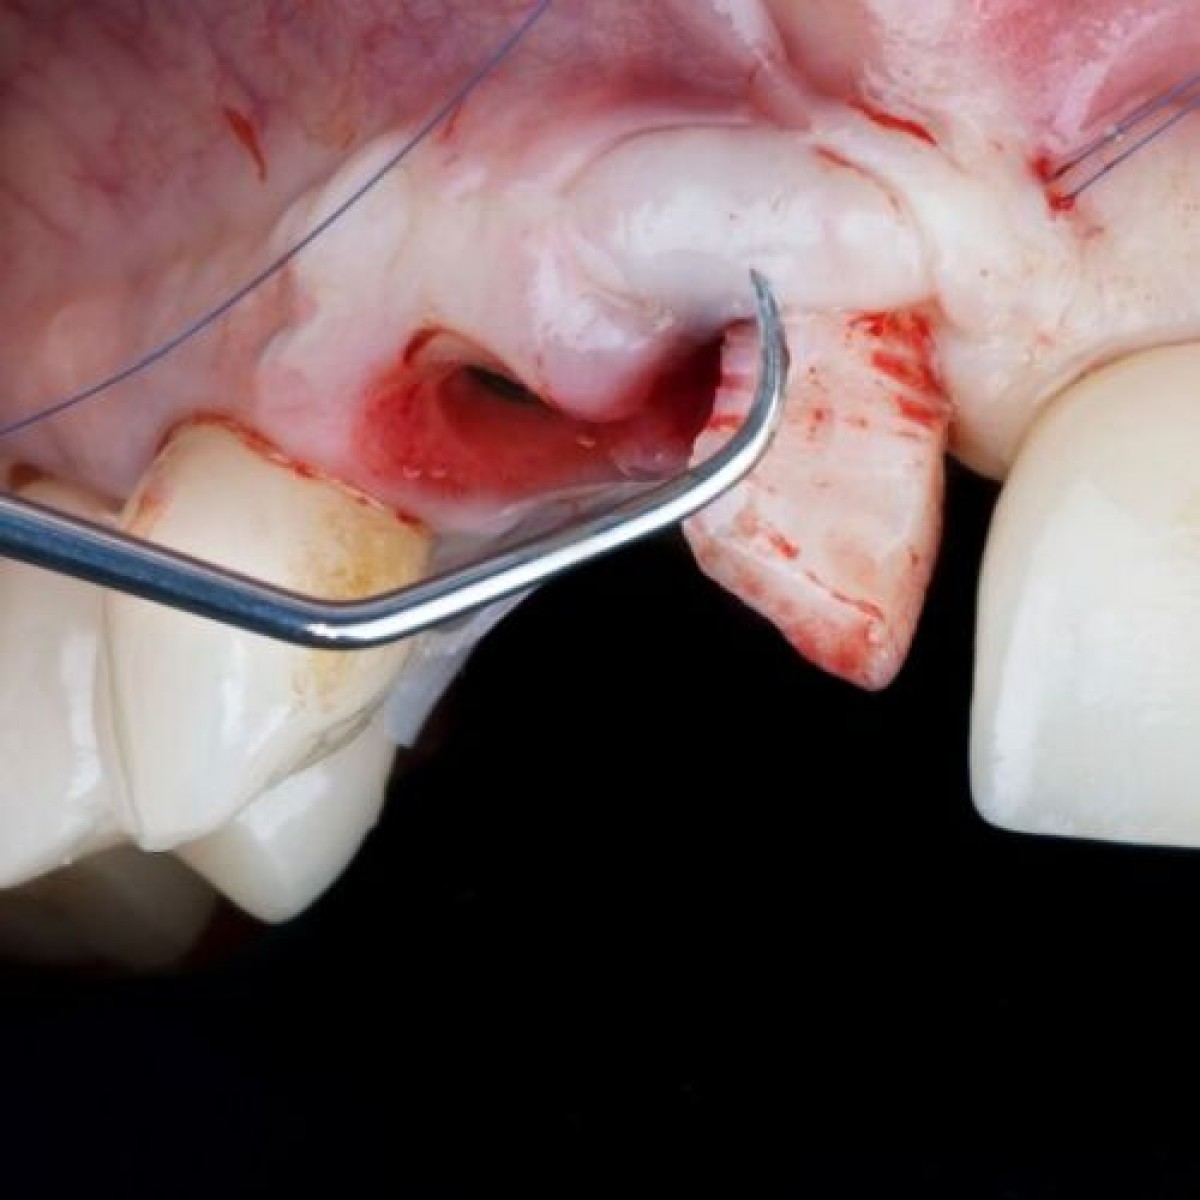

Thirty cadavers which were offered by the Institute of Anatomy for the purpose of running oral surgery and implantology courses were embalmed in the technique described by Thiel. On each cadaver, dissection of soft and hard tissue and implantological procedures were performed according to a structured protocol by each course participant. The conservation of fine anatomical structures and the suitability of the embalmed tissue for dissecting, drilling, and suturing were observed and photographically documented.

By means of the Thiel embalming technique, oral surgery and implantological procedures could be performed under realistic conditions similar to the living body. Due to the conservation procedure, preparations could be carried out without any time limit, always maintaining the same high quality of the tissue. The maxillary sinus membrane, mucosa, bone, and nerves could be exposed and allowed dissecting, drilling, and suturing even after weeks like fresh specimens.

The Thiel embalming method is a unique technique which is ideally suited to practice and teach oral surgery and implantology on human material.